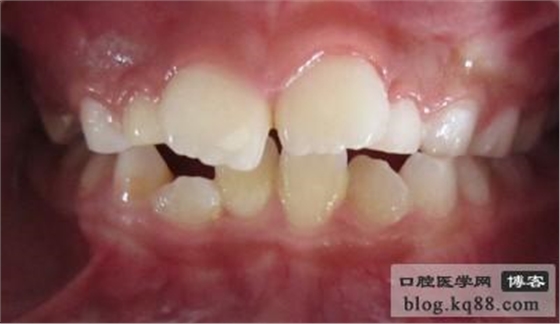

術(shù)后1個半月天復(fù)診圖片資料